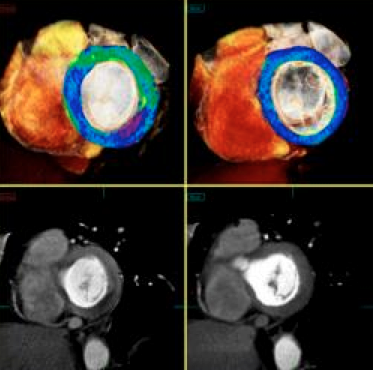

A CT myocardial perfusion image set showing perfusion defects in a color-coded iodine map and seen as darker areas of low contrast in the images below.

A key component of this transformation is a new super-computing technology called CT-fractional flow reserve (FFR), which may offer a noninvasive alternative to catheter-based FFR, the current gold standard for determining if a stent is required for a particular lesion. Experts at SCCT said this, combined with CT myocardial perfusion imaging, will be more accurate and help eliminate the need for nuclear perfusion imaging.